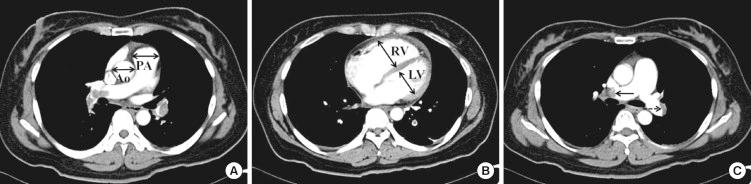

This study was performed to compare clinical and imaging parameters and prognosis of unprovoked pulmonary embolism (PE), provoked PE with reversible risk factors (provoked-rRF), and provoked PE with irreversible risk factors (provoked-iRF) in Koreans. Three hundred consecutive patients (mean age, 63.6 ± 15.0 yr; 42.8% male) diagnosed with acute PE were included. The patients were classified into 3 groups; unprovoked PE, provoked-rRF, and provoked-iRF; 43.7%, 14.7%, and 41.7%, respectively. We followed up the patients for 25.4 ± 33.7 months. Composite endpoint was all-cause mortality and recurrent PE. The provoked-iRF group had significantly higher all-cause mortality, mortality from PE and recurrent PE than the unprovoked and provoked-rRF groups (P < 0.001, P < 0.001, and P = 0.034, respectively). Prognostic factors of composite endpoint in the unprovoked group were high creatinine (> 1.2 mg/dL; P < 0.001; hazard ratio [HR], 4.735; 95% confidence interval [CI], 1.845-12.152), C-reactive protein (CRP; > 5 mg/L; P = 0.002; HR, 5.308; 95% CI, 1.824-15.447) and computed tomography (CT) obstruction index (P = 0.034; HR, 1.090; 95% CI, 1.006-1.181). In conclusion, provoked-iRF has a poorer prognosis than unprovoked PE and provoked-rRF. Renal insufficiency, high CRP, and CT obstruction index are poor prognostic factors in unprovoked PE.

本研究旨在比较韩国人群中特发性肺栓塞(PE)、有可纠正危险因素的PE(provoked-rRF)和有不可纠正危险因素的PE(provoked-iRF)的临床和影像学参数及预后。纳入 300 例连续确诊为急性 PE 的患者(平均年龄 63.6±15.0 岁,42.8%为男性)。患者分为三组:特发性 PE、有可纠正危险因素的 PE 和有不可纠正危险因素的 PE,分别占 43.7%、14.7%和 41.7%。我们对患者进行了 25.4±33.7 个月的随访。复合终点为全因死亡率和复发性 PE。与特发性和有可纠正危险因素的 PE 组相比,有不可纠正危险因素的 PE 组的全因死亡率、PE 死亡率和复发性 PE 发生率显著更高(P<0.001、P<0.001 和 P=0.034)。特发性组复合终点的预测因素包括血肌酐升高(>1.2mg/dL;P<0.001;危险比[HR],4.735;95%置信区间[CI],1.845-12.152)、C 反应蛋白(CRP;>5mg/L;P=0.002;HR,5.308;95%CI,1.824-15.447)和 CT 阻塞指数(P=0.034;HR,1.090;95%CI,1.006-1.181)。总之,有不可纠正危险因素的 PE 的预后较特发性 PE 和有可纠正危险因素的 PE 差。肾功能不全、高 CRP 和 CT 阻塞指数是特发性 PE 的不良预后因素。